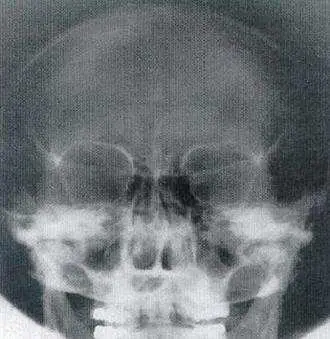

本題圖片為頭顱正位 X 光影像(後前位方向),影像顯示:

- 頭顱整體輪廓:可見頭顱正面骨結構,雙側對稱

- 眼眶(orbit):雙側眼眶清楚可見,形態完整

- 岩骨脊(petrous ridge)投影位置:岩骨脊投影於眼眶下三分之一處(lower third of the orbit),這是 Caldwell method 最重要的辨識特徵

- 篩竇(ethmoid sinus)與額竇(frontal sinus):可見顱面中央部位的竇腔結構

- 上顎骨與顴骨:下方可見上顎牙列及顴骨弓結構

- 鼻骨與鼻中隔:中央鼻部結構可辨認

影像中岩骨脊明顯投影在眼眶下方三分之一範圍,不遮蓋額竇,符合 Caldwell method(PA Axial,中央射線向尾端傾斜 15°)的典型影像特徵。